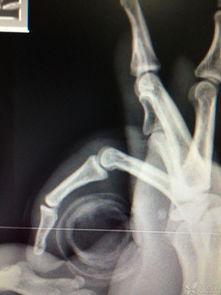

首先,让我们来看看手骨折的初期形态。骨折后的手,就像被大自然开了一个玩笑,原本整齐的骨骼变得歪歪扭扭,让人看了不禁心疼。有的骨折部位明显,骨头错位,甚至可以看到明显的裂缝;有的则较为隐蔽,需要仔细观察才能发现。这些手骨折的图片,让人不禁为受伤者的痛苦而感到惋惜。

2. 手术矫正:对于一些复杂的骨折,手术矫正是必不可少的。手术过程中,医生会小心翼翼地调整骨折部位,使其恢复到正常状态。手术后的手,会留下明显的疤痕,但这也是治愈的证明。